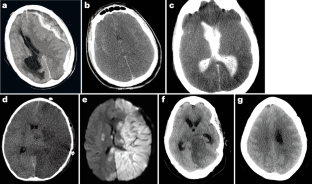

Acceptable ancillary tests, which are only to be used when a complete clinical evaluation is not possible or safe, comprise tests of cerebral blood flow, such as four-vessel catheter angiography, radionuclide perfusion scintigraphy and transcranial Doppler ultrasonography (in adults only). EEG is no longer accepted as an ancillary test, and the most recent US guidelines and the WBDP do not permit the use of CT angiography.

The authors are grateful to A. Sarwal and M. Abdalkader for their assistance with the ultrasound and neuroimaging images for the figures.